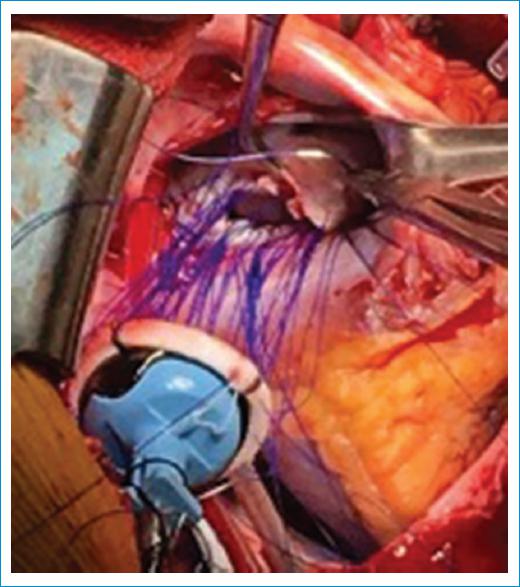

Se decidió realizar procedimiento quirúrgico por esternotomía media; se hizo canulación de aorta, aurícula derecha y vena cava inferior, para iniciar protocolo de cardioplejía, durante el cual se encontró cardiomegalia de grado IV con predominio de cavidades derechas, válvula aórtica trivalva con defecto en la zona de coaptación de aproximadamente 1 cm, obtuso marginal con zona de cicatrización, válvula mitral con insuficiencia grave, mala coaptación de valvas y hendiduras en valva anterior y posterior que asemejan subdividir la válvula en cuatro valvas (Fig. 2). Se procedió con anastomosis distal de obtuso marginal a vena safena reversa, y se hizo sutura continua (Fig. 3). Se realizó recambio por válvula aórtica mecánica St Jude 21 (Fig. 4) con puntos separados, seguido de recambio de válvula mitral con válvula mecánica St Jude 31 con sutura continua intermitente (Fig. 5), y posteriormente se inició el protocolo de salida de derivación cardiopulmonar.